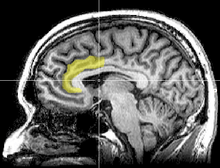

As a relatively new technology, fMRI has only recently been used to assess brain state changes during meditation. Recent studies have shown heightened activity in the anterior cingulate cortex, frontal cortex, and prefrontal cortex, specifically in the dorsal medial prefrontal area during Vipassana meditation.[7] Similarly, the cingulate cortex and frontal cortex areas were shown to have increased activity during Zen meditation.[8] Both studies comment on the possibility that these findings could indicate some state of heightened voluntary control over attention during mindfulness meditation. Review works by Cahn and Chiesa state that these results indicate consistency in meditation’s effect on these regions of the brain, citing a multitude of other studies spanning other meditative disciplines, but mention the need for further investigation with better controls.[4][6]